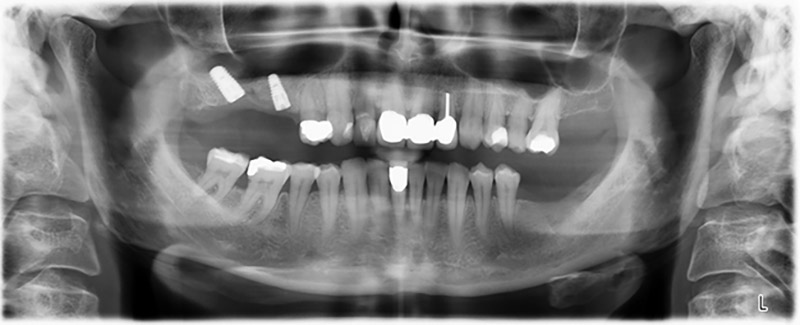

Etwa sechs Monate nach Extraktion der Zähne 16 und 14 wurde zur Planung und Risikominimierung eine digitale Volumentomografie (DVT, Planmeca) erstellt. Hierbei wurde deutlich, dass der Knochen sich nicht in der gewünschten Quantität regeneriert hat (Abb. 2 bis 7).

Um eine festsitzende Versorgung auf mindestens zwei Implantaten zu gewährleisten, ist eine Sinusbodenelevation sowohl in Regio 16 als auch in Regio 14 erforderlich. Da in diesem Fall das Restknochenangebot extrem gering ist, müsste ein verhältnismäßig großer Knochenaufbau durchgeführt werden. Große Knochenaufbauverfahren sind invasiv, mit einer höheren Patientenmorbidität verbunden, zeitintensiv und kostspielig. Die Vorhersagbarkeit der Behandlungsresultate ist geringer und das Misserfolgsrisiko höher. Vor dem Hintergrund dieser Nachteile, wurde die Patientin über eine herausnehmbare Alternative aufgeklärt, die sie jedoch konsequent ablehnte.